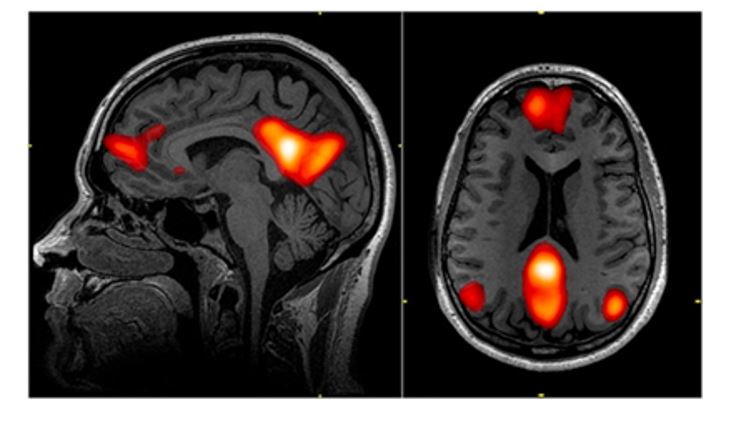

では、このアイデンティティとは脳の中でどのようなものとして処理されるのだろうか。いくつかの研究から、アイデンティティにはデフォルトモードネットワークと呼ばれる脳の仕組みが関わっていることが考えられている。

デフォルトモードネットワークとは、以下の図に示すように、脳の中でも内側領域が中心となって構成されたものである。これらの脳領域は、自分に関連する刺激(自分の名前や自分の故郷)に反応して活動したり、あるいは自分の過去を振り返るような時に活動したりすることが分かっている。

そしでデフォルトモードネットワークの中でも前帯状皮質の前方領域(下図PACC)が特にアイデンティティ認識の中心であると考えられている1)。